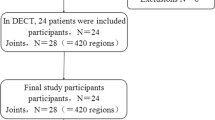

We retrospectively identified all patients with suspected gout who underwent DECT in the period from September 2011 through July 2014 and additionally had an MRI of the same anatomical region. All patients had an unclear clinical presentation and suspicion of gouty arthritis that occurred either when first presenting at our hospital or later in the course of the treatment. DECT was performed to search for gouty tophi, and MRI in clinical routine to detect inflammatory changes. The report database and hospital PACS (picture archiving and communication system) were used to find those examinations. From the 24 patients who met these criteria, we selected those who had an interval of 3 months or less between DECT and MRI. Eleven patients (six men and five women aged from 45 to 81 years (mean age, 62.2 years) with an interval of 0–82 days (mean, 40 days) between examinations met our criteria and were included. Details of the study population are summarized in Table 1.